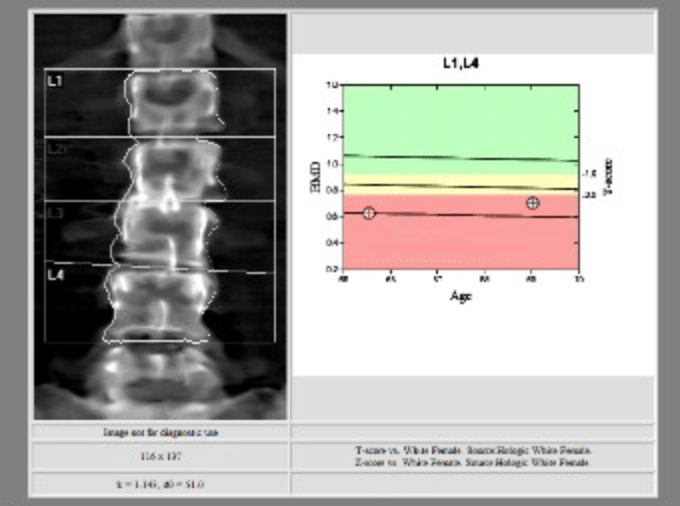

case in point: just yesterday morning, when word arrived that my latest bone scan report (after a year of monthly pokes in both arms, in hopes of building up my chalky bones into something more substantial), had been filed by the radiologist, and was ready for viewing, i opened said report and nearly toppled.

there, in black and white, the impolite and overwrought label they’d pinned to my condition: not only was i osteoporotic in the extreme, they went one descriptor further, dipping deep into their shallow pool and dubbed my affliction, senile osteoporosis.